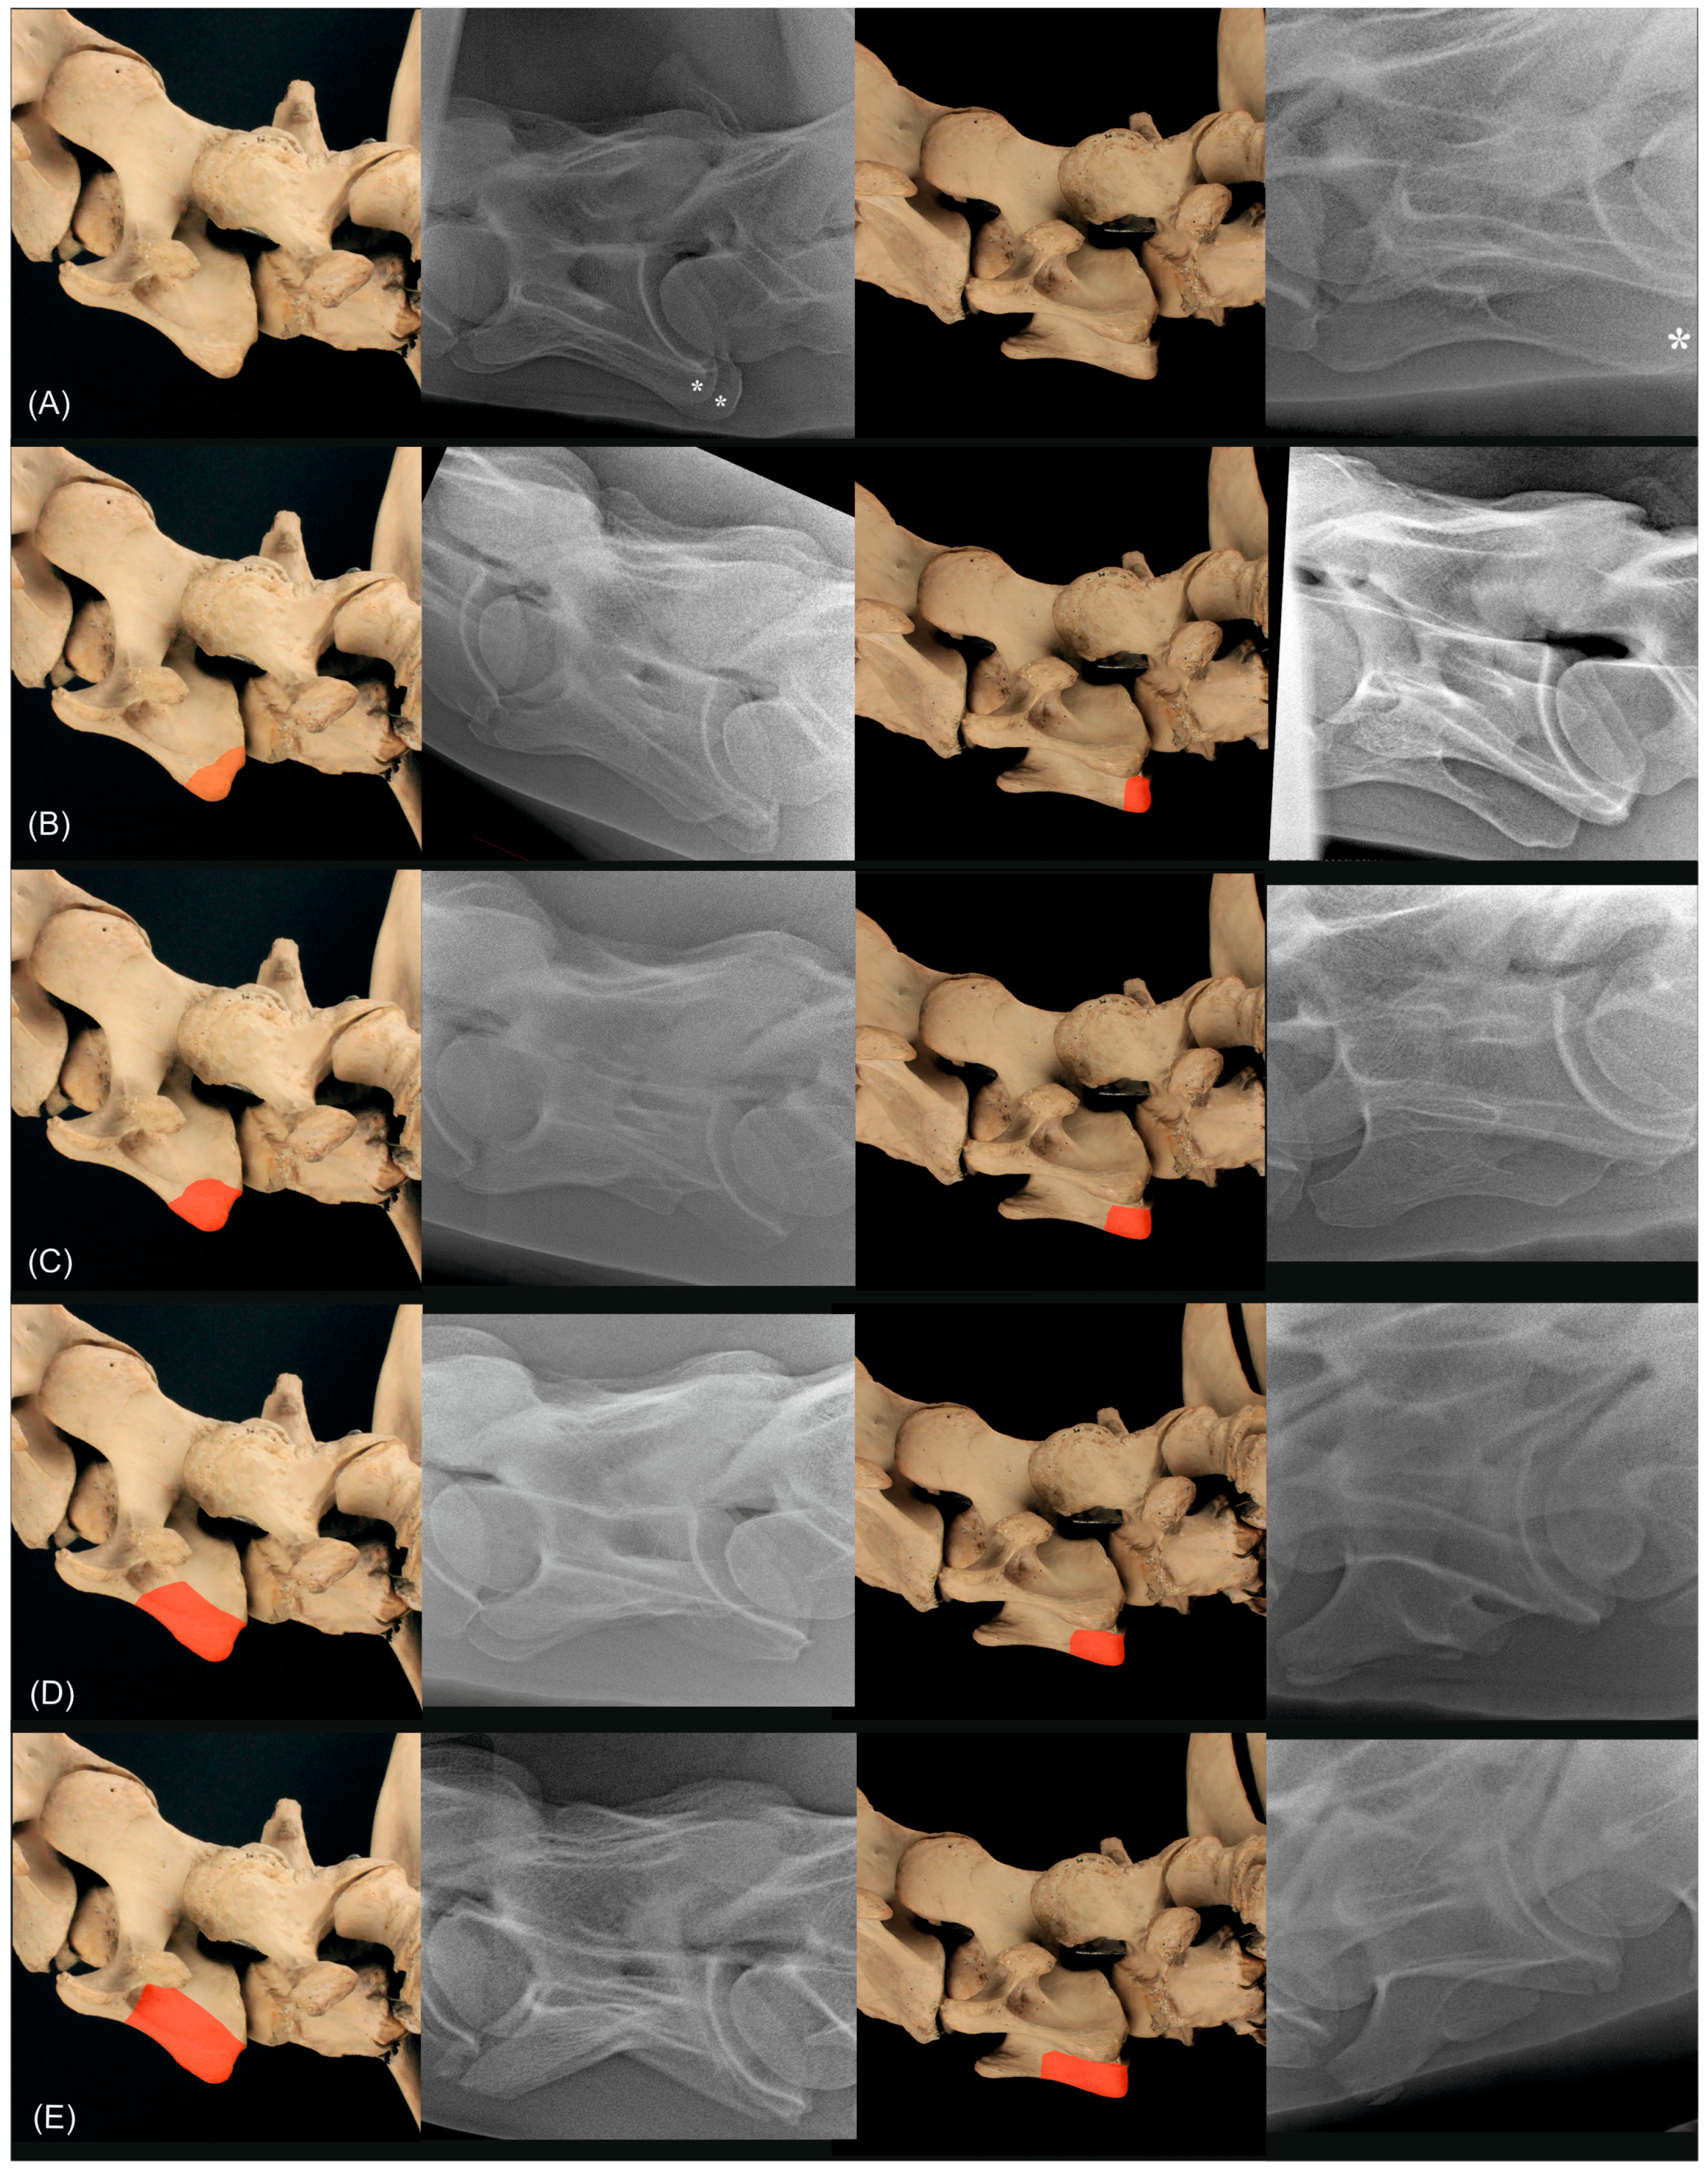

2.3. Radiographic Method

2.4. Classification System